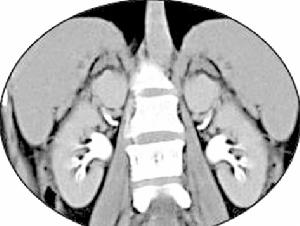

腎性失鎂是一種罕見的腎小管功能障礙疾病。引起腎性失鎂的疾病很多,可分為原發性和繼發性,多為繼發性。原發性目前已知的有兩型,一型為單純性腎小管重吸收鎂功能障礙,此型又稱近端型多伴胺基酸尿,提示功能缺陷在近曲小管;另一型為遠端型是腎小管重吸收鎂功能障礙伴鉀轉運異常,常伴腎失鉀及低鉀血症,本型功能缺陷可能在遠曲小管。本症兩型均有家族性,是一種罕見的常染色體隱性遺傳疾病。

通過了解病史,原發者常有家族史,繼發者常有固有疾病表現。根據典型臨床表現,即尿鎂增多、伴胺基酸尿或糖尿,低鎂血症或伴有低鉀血症、低鈣血症等有關實驗室檢查可考慮本病診斷。

腎性失鎂1.尿液檢查 尿鎂明顯增多>4mmol/L(尿中低於12mg/24h為缺鎂之症)伴有低鉀血症者,可有尿鉀增多。並有胺基酸尿及糖尿,

2.血液檢查 血鎂降低,血鈣降低(PTH分泌和作用障礙所致),血鉀降低,腎小管濃縮功能障礙輕度代謝性鹼中毒血漿腎素活性增高,但醛固酮含量正常,腎小球濾過率正常。